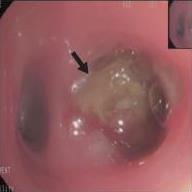

• 侵袭性肺真菌病的支气管镜表现及介入治疗效果

2025, 31(9):81-90. DOI: 10.12235/E20250317

摘要 (112) HTML (56) PDF 6.06 M (77) 评论 (0) 收藏

摘要:目的 探讨侵袭性肺真菌病(IPFD)的支气管镜表现,并评估介入治疗的安全性和疗效。方法 回顾性分析2018年5月12日-2025年5月12日于该院行支气管镜检查的35例IPFD患者的临床资料,观察IPFD的支气管镜表现及介入治疗效果。结果 共收集35例患者临床资料。其中,男22例,女13例,患者年龄(53±14)岁。基础疾病包括:血液系统恶性肿瘤10例,长期应用糖皮质激素者5例,2型糖尿病者4例,肺部恶性肿瘤2例,器官移植1例。胸部CT显示:肺部病变累及单肺叶者19例,累及多肺叶者16例。支气管镜下表现主要为:黏膜充血水肿29例(82.9%)、坏死物堵塞管腔22例(62.9%)、大量黏稠脓性分泌物17例(48.6%)、支气管部分狭窄或闭塞16例(45.7%)、黏膜坏死9例(25.7%)、黏膜出血5例(14.3%)、真菌球3例(8.6%)。其中,32例(91.4%)接受全身性抗真菌治疗,17例(48.6%)接受支气管镜局部两性霉素B灌注治疗,10例(28.6%)采用活检钳钳除病灶,6例(17.1%)采用冷冻探头冻取病灶,4例(11.4%)接受氩气刀治疗。28例(80.0%)临床症状明显改善,肺部影像学病灶缩小或消退;4例(11.4%)病灶稳定;3例(8.6%)未完成治疗。结论 IPFD多见于免疫抑制宿主,支气管镜常表现为:坏死物堵塞管腔、伴脓性分泌物、支气管管腔狭窄和局部黏膜充血水肿或坏死。全身抗真菌药物联合支气管镜下介入治疗,安全性高,且疗效好。